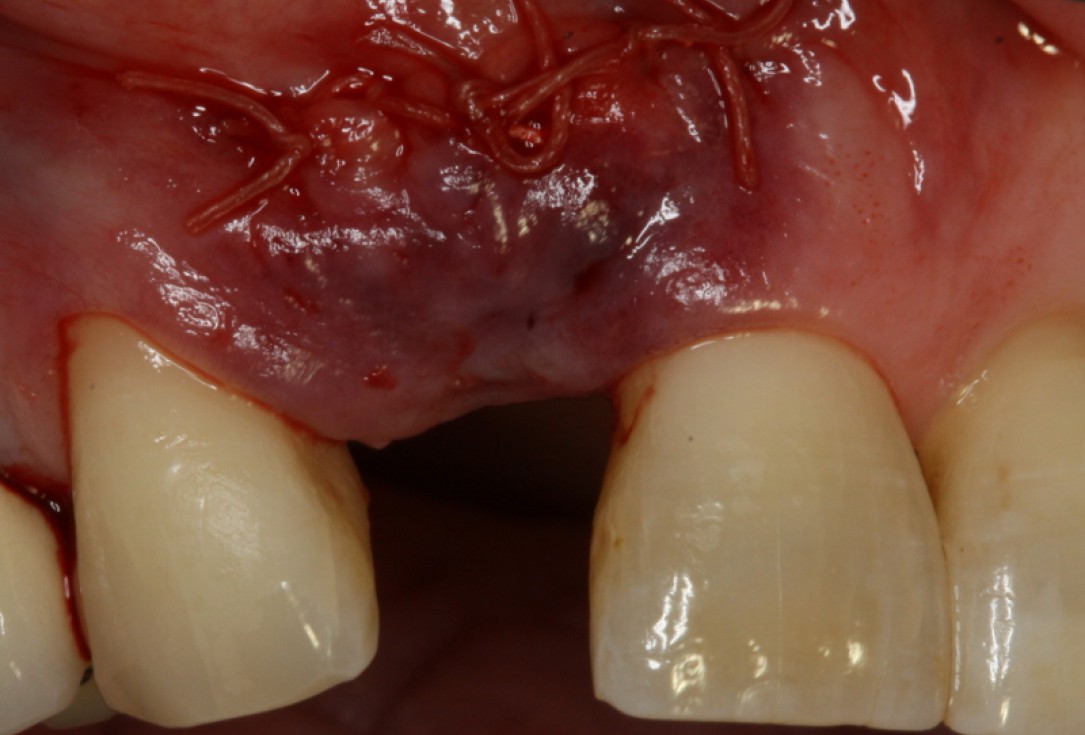

10/20 - wound closureGBR with maxresorb® & Jason® membrane - Prof. Dr. Dr. D. Rothamel